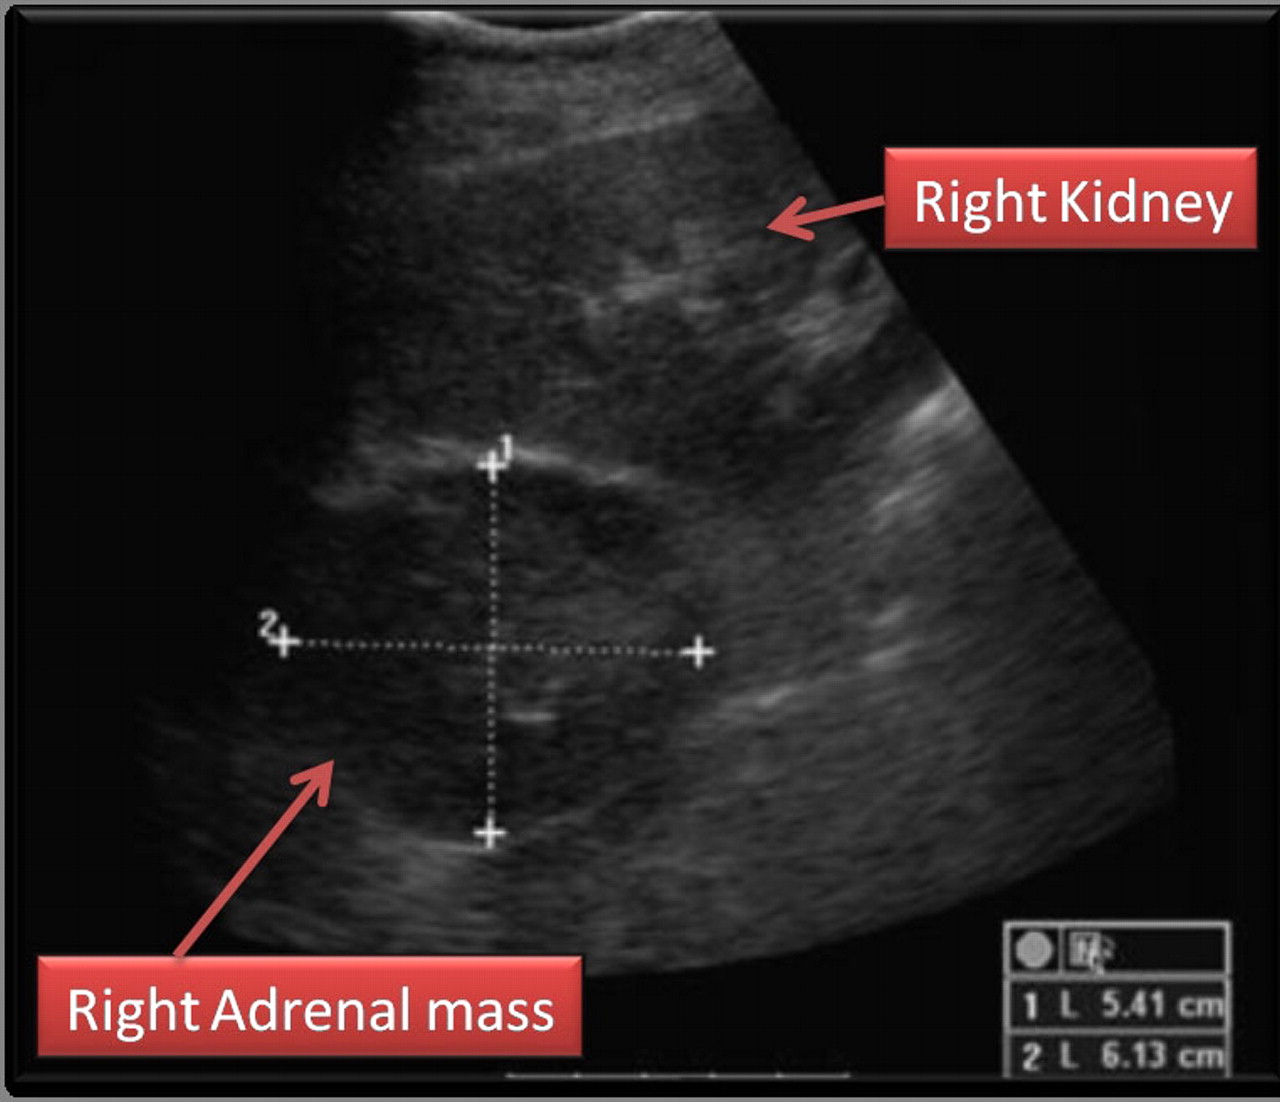

Ultrasound is sometimes used in the diagnosis of adrenal tumors. Ultrasounds use sound waves to form a picture of the inside of the body. At times, it can be difficult to tell if an adrenal tumor is an adenoma or a cancer. For tumors that are larger than 3 cm, ultrasound is a good method of telling the difference between the two.